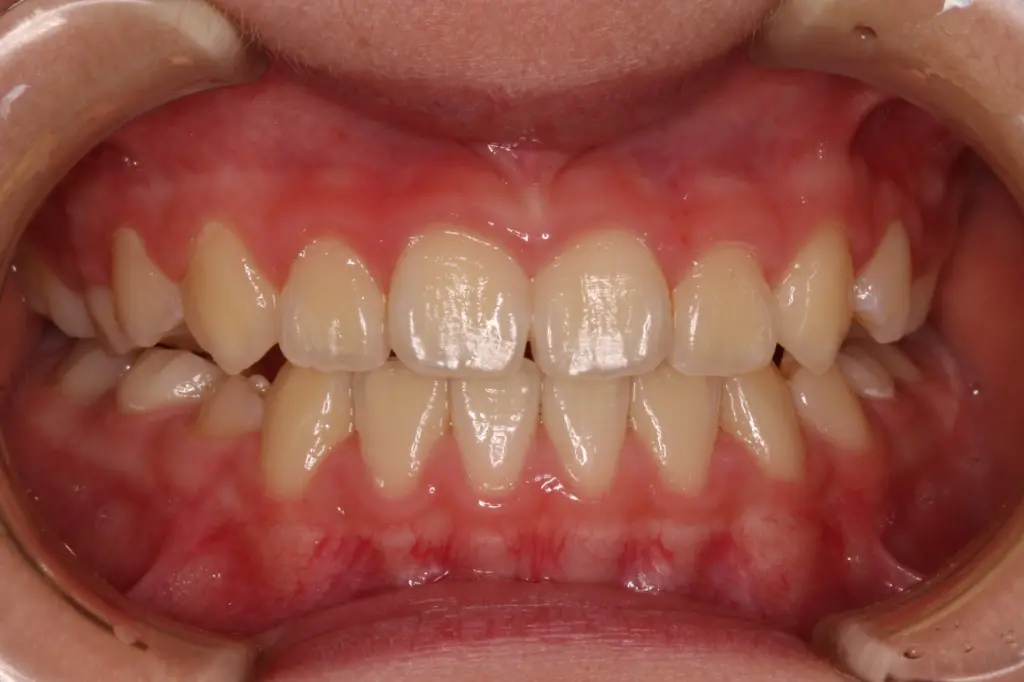

3年経過時 治療3年後の状態

【安定と成長】

反対咬合の後戻りはなく、永久歯への生え変わりも順調です。顎も正しく成長し、安定した噛み合わせが続いています。